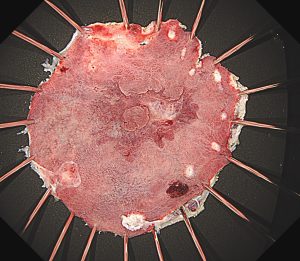

早期胃癌(SM浸潤がん)ESD

早期大腸癌(LST-G)ESD